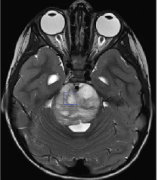

弥漫性脑桥胶质瘤通常表现为多脑神经麻痹、长束征和共济失调。通常,这些肿瘤会导致脑桥扩大50%以上,并可能渗透到髓质或中脑。诊断基于磁共振成像上弥漫性、T2加权、高强度脑...